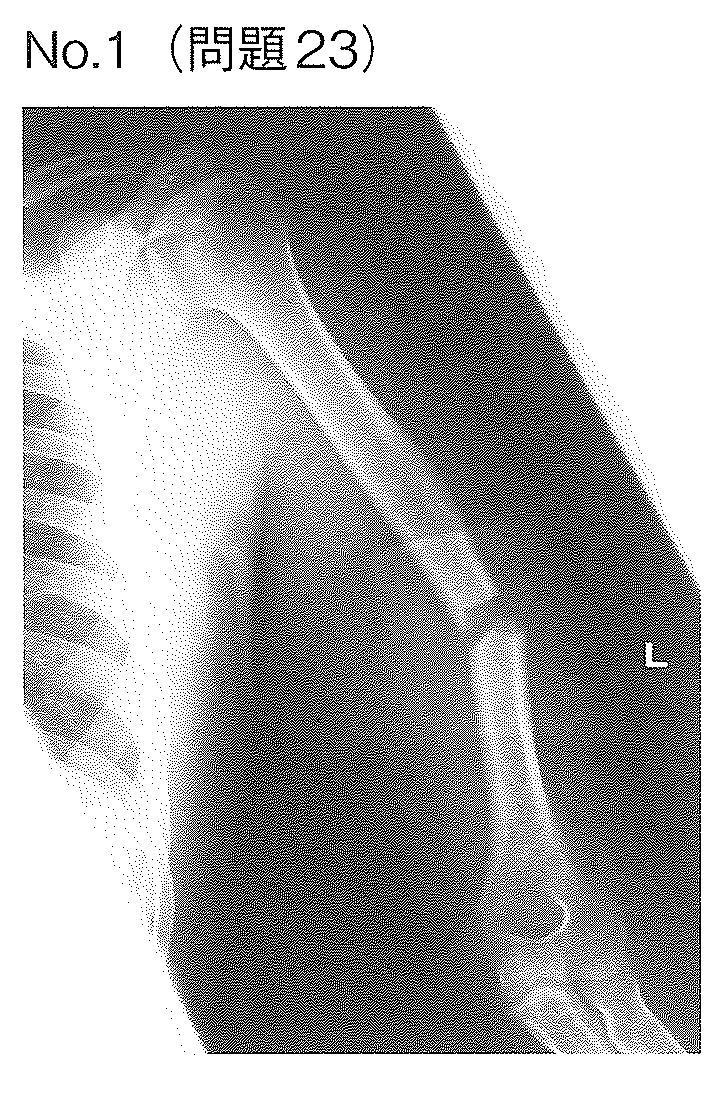

33回国家試験 午後23

20歳の男性。高速道路で自動車運転中に横転して受傷した。運搬先の病院で撮影した左上腕の単純エックス線写真(別冊 No.1)を別に示す。左手に運動麻痺がみられ、急性期治療後も麻痺は残存している。使用すべき装具はどれか。